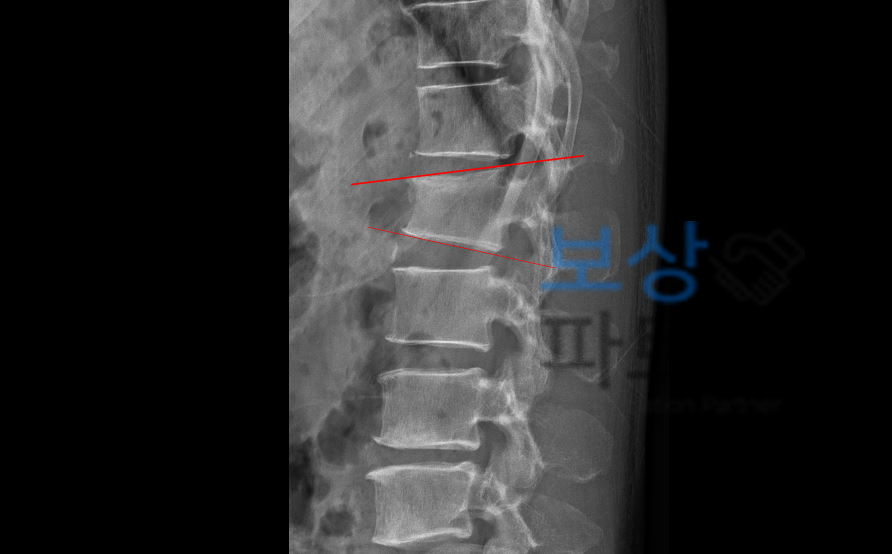

정말 안타깝게도 많은 분들이 나는 수술안했기 때문에 혹은 통증이 없고 뼈도 잘 붙어서 나는 장해가 남지 않았다고 생각하십니다. 척추압박골절은 원통모양의 척추체가 위아래로 찌그러지듯 골절됩니다.

중요한 것은 골절된 척추체로 인해 척추체의 압박률 증가와 더불어 기존 척추 S만곡에 전만, 후만 측만으로 변화를 주게 되는데요,

보험약관에서는 척추압박골절 비수술이어도 허리보조기 착용하며 보존적 치료 해도! 위 압박률과 각도 변형이 되었다면 후유장해가 영구적으로 잔존했다고 보며 후유장해 보험금을 지급해줍니다. 단돈 몇십만원이 아니라 가입 담보 금액에 따라서 적게는 수백에서 많게는 수 천 만원 입니다.